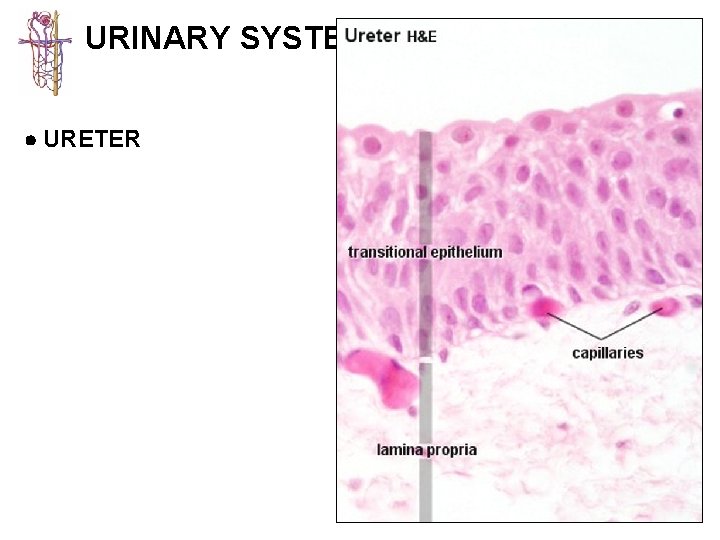

URINARY SYSTEM KIDNEY CALYCES/ URETER BLADDER URETHRA 1 - mucosa lined with transitional 2 -epithelium usually lacking submucosa 3 - muscularis best developed in ureters (2 -3 layers) and bladder (3 layers)

URINARY SYSTEM URETER

URINARY SYSTEM URETER

URINARY SYSTEM BLADDER transitional epithelium